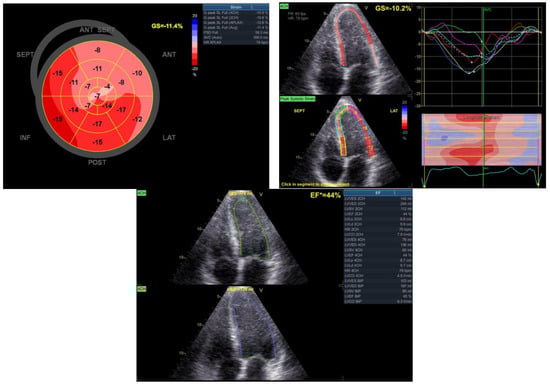

After completing the cardiovascular rehabilitation program, an echocardiography was performed to assess the cardiac status. The results revealed a modest improvement in the systolic function of the left ventricle (EF = 44%). Additionally, slight hypokinesia of the interventricular septum and anterolateral wall and apex dyskinesia (aneurysm) were observed. Furthermore, mild regurgitation was noted in the mitral and tricuspid valves (Figure 9).

Figure 9. Echocardiographic aspects observed after the rehabilitation program.